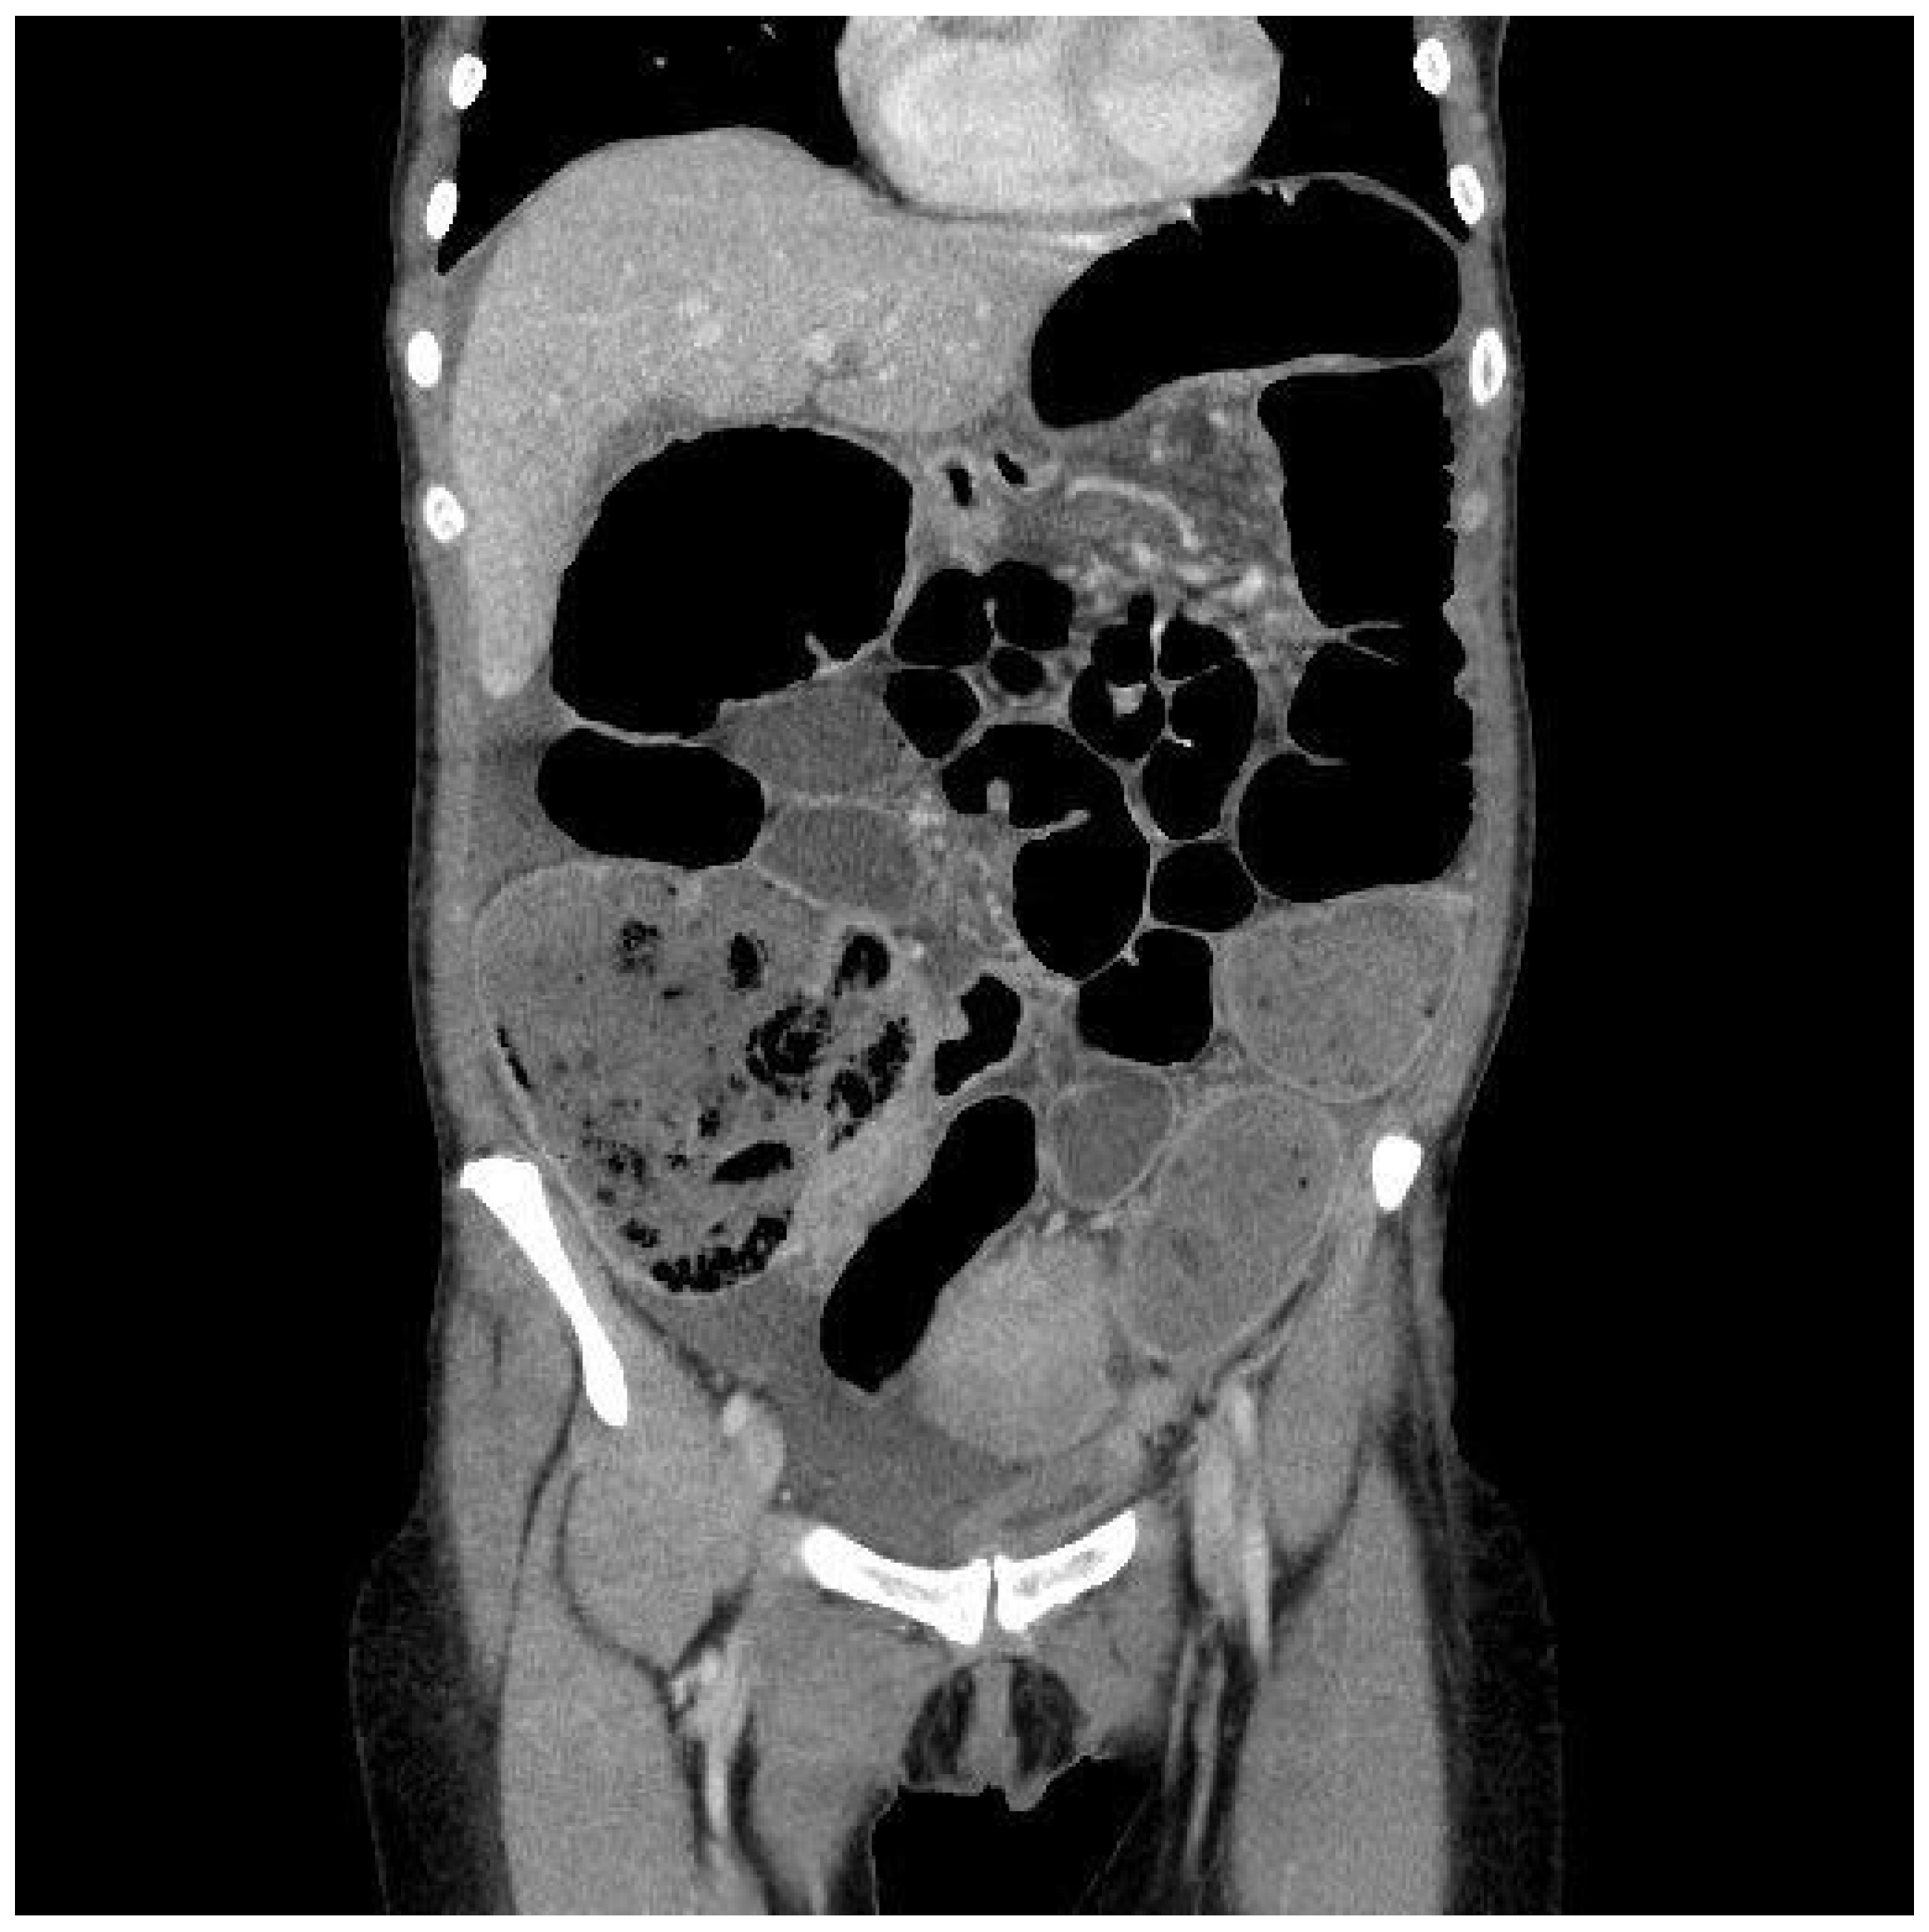

The first patient, a 48-year-old woman, came to the general Emergency Room in March 2023. She had been experiencing abdominal pain, distention, and intestinal obstruction a few days before her visit. Importantly, she exhibited no signs of fever and had no notable medical history. A CT scan showed an enlarged right adnex with multiple fluid-filled cysts (Figure 1). The left side of the uterus appeared thickened and was in continuity with the left bladder wall (Figure 2). Moreover, the colonic wall displayed thickening and hyperemia. The abdominopelvic area contained heterogeneous material with fluid pockets and signs of peritoneal fluid effusion. Consequently, the patient was referred for a gynecological evaluation. Clinical findings indicated abdominal distension accompanied by pain upon palpation. A bimanual examination uncovered indeterminate solid tissue. The ultrasound revealed a thin, linear endometrium and an enlarged right ovary, while the left ovary was significantly adhered to the sigmoid colon. Laboratory results showed an elevated white blood cell count (15.02 × 103/µL) and a higher C-reactive protein level (CRP 40.49 mg/L). Due to the high suspicion of gynecological malignancy, the patient underwent surgical procedures including laparotomic hysterectomy, bilateral tubo-oophorectomy, sigmoid resection with ileostomy, removal of the round ligament, omentectomy, appendectomy, and peritoneal biopsies. Intraoperative observations noted substantial adhesions involving the uterus, ovaries, and the sigmoid–rectal tract, along with mild ascitic effusion. An intraoperative histological assessment identified Actinomyces colonies. Despite this, the extensive disease burden suggested that demolitive surgery was warranted. Histological examination of the specimen diagnosed pelvic inflammatory disease featuring a tubo-ovarian abscess, revealing necrotic tissue with inflammatory characteristics, significant inflammation, and Actinomyces colonies mainly in the round ligament and right ovary. As a complication, the patient required a bilateral pyelostomy because of a left ureteral fistula linked to pelvic effusion stemming from past inflammation and vesicoureteral reflux. Nine months later, she underwent ano–rectal fistula repair. She received three months of antibiotic therapy with Amoxicillin and Doxycycline, followed by an additional eleven months of Amoxicillin, depending on complications after surgery. Fourteen months post-initial procedure, an X-ray with barium enema/CT scan was performed, indicating significant remission of complications. Currently, she is asymptomatic and continues to attend follow-up appointments monitoring.

Figure 1.

Frontal CT scan. It is possible to appreciate the right adnex mass with disomogeneous solid and cystic content. This is a common aspect between Actinomycosis and ovarian cancer. Bowel dilatation should make clinicians suspect neoplastic sub-occlusion and omentum suffusion should mimicry neoplasm dissemination, leading to a misdiagnosis.

Considering the imaging findings, the pelvic masses observed in both cases presented characteristics indicative of a potential malignancy. The masses were primarily associated with adnexal structures, exhibiting either cystic or solid contents and forming adhesions with adjacent anatomical entities. Although the ultrasound examination may have yielded nonspecific results, the CT scan also displayed images suggestive of gynecological malignancy. It would be improbable to suspect a benign pathology based solely on clinical examination and imaging findings, corroborating the existing literature.